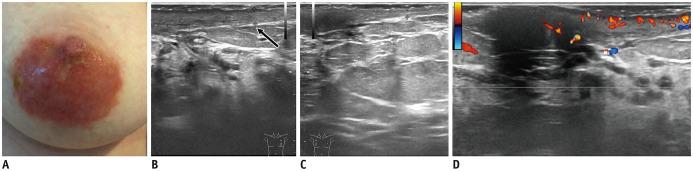

Ultrasound (US) is an attractive diagnostic approach to identify both common and uncommon nipple pathologies, such as duct ectasia, nipple abscess, nipple leiomyoma, nipple adenoma, fibroepithelial polyp, ductal carcinoma (restricted to nipple), invasive carcinoma, and Paget's disease. US is the reliable first-line imaging technique to assess nipple pathologies. It is useful to identify and characterize nipple lesions. Additionally, we have presented the mammography and MRI outcomes correlated with histopathologic features for the relevant cases.